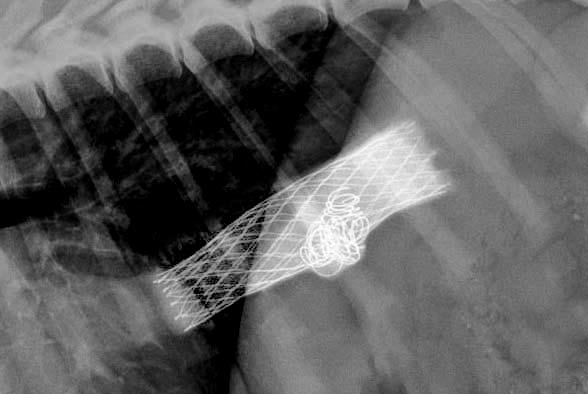

Tracheal collapse is a chronic progressive respiratory disease most commonly seen in mature toy and small breed dogs. Dynamic airway obstruction is caused by chondromalacia,